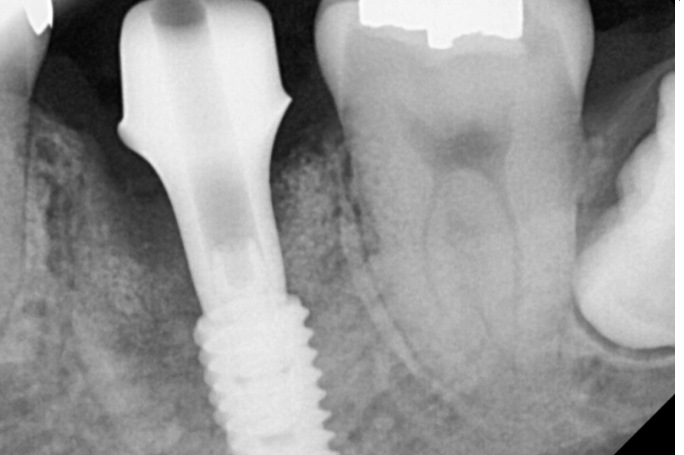

왼쪽 아래 수술 시

치아 염증으로 이미 뼈가 많이 녹아

웅덩이처럼 파여 있었는데요.

내비게이션 임플란트 장비를 사용하여

뼈가 많은 부위에 식립할 수 있었습니다.

240208

수술 후 한 달 뒤

뼈와 잘 붙어서 바로 머리를 올렸습니다.

하악은 일반적으로 3개월 정도 기다리는데요.

저희가 뼈와 임플란트가 잘 붙었는지

확인 후 머리를 만들어드렸습니다.

수술 후 임플란트와 뼈가 얼마나 잘 붙었는지

▼수치화해주는 기계▼를 통해 검사합니다.

해당 환자분은 한 달 뒤에

검사를 해보았을 때

뽄을 뜨기에 충분히 수치가 나와서

머리 만드는 작업을 바로 진행했습니다.